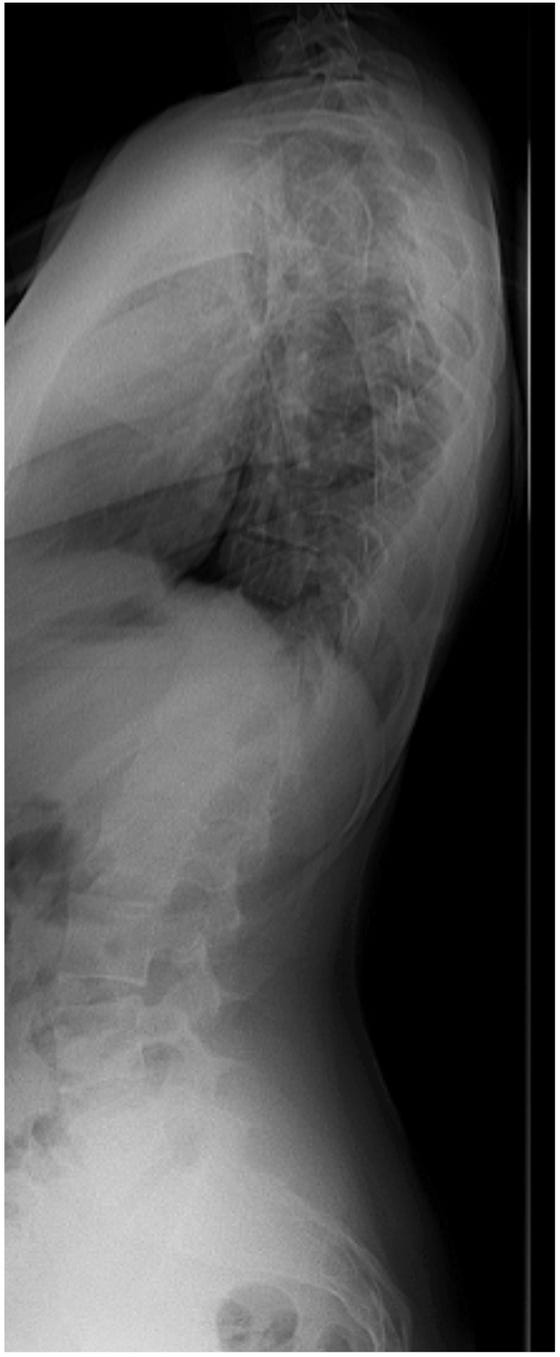

De wervelkolom wordt vastgezet met behulp van metalen staven en schroeven. Op sommige plaatsen maakt de chirurg de wervels beter passend door wat bot weg te halen. Dit zorgt ervoor dat alles stevig vast groeit.

Op de röntgenfoto’s kun je zien hoe de wervelkolom er voor en na de operatie uit ziet.

Figuur 1: scoliose voor de operatie

Figuur 2: scoliose na de operatie